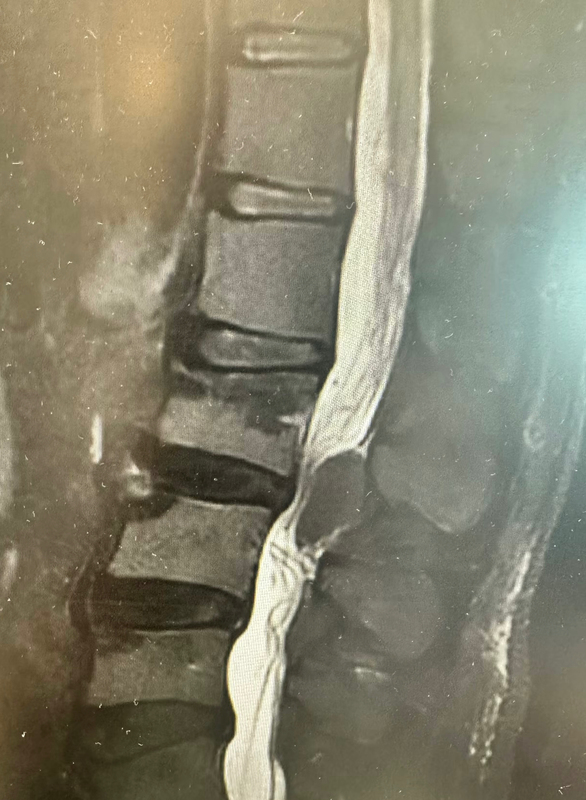

腰椎椎管內(nèi)長了腫瘤,壓迫神經(jīng)導致下肢疼痛不適。相信大家第一次看到這些片子的時候,第一反應就是這個病人是不是可能已經(jīng)癱瘓了,畢竟因為片子上神經(jīng)壓迫非常重,神經(jīng)已經(jīng)被壓成一條細線了,而實際上病人還能下床活動,還能行走,只有可耐受的下肢疼痛不適。這時候就不得不感嘆造物者的神奇了,我們都知道脊髓神經(jīng)受到壓迫以后,輕者肢體麻木,重著可能無力癱瘓,而且再生能力極差,截癱以后大部分很難恢復正常,但是,脆弱的脊髓神經(jīng)分布在第二腰椎以上的脊柱椎管內(nèi),到第二腰椎以下就是馬尾神經(jīng)了,對壓迫的耐受度更高,爹爹的椎管內(nèi)大腫瘤剛好在第二腰椎椎體以下水平,第二第三腰椎之間,這也是為何腫瘤會長如此大才發(fā)現(xiàn)的原因。經(jīng)過科學縝密的術(shù)前評估,術(shù)中小心仔細的操作,術(shù)中完切除了腫瘤。